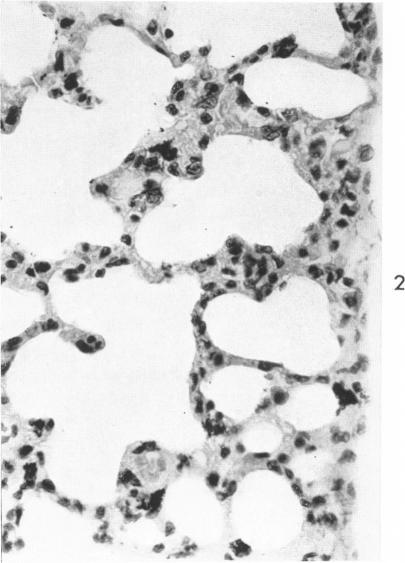

The disposal of inhaled particulate matter; a unifying hypothesis.

Am J Pathol. 1963 Feb;42(2):119-35.